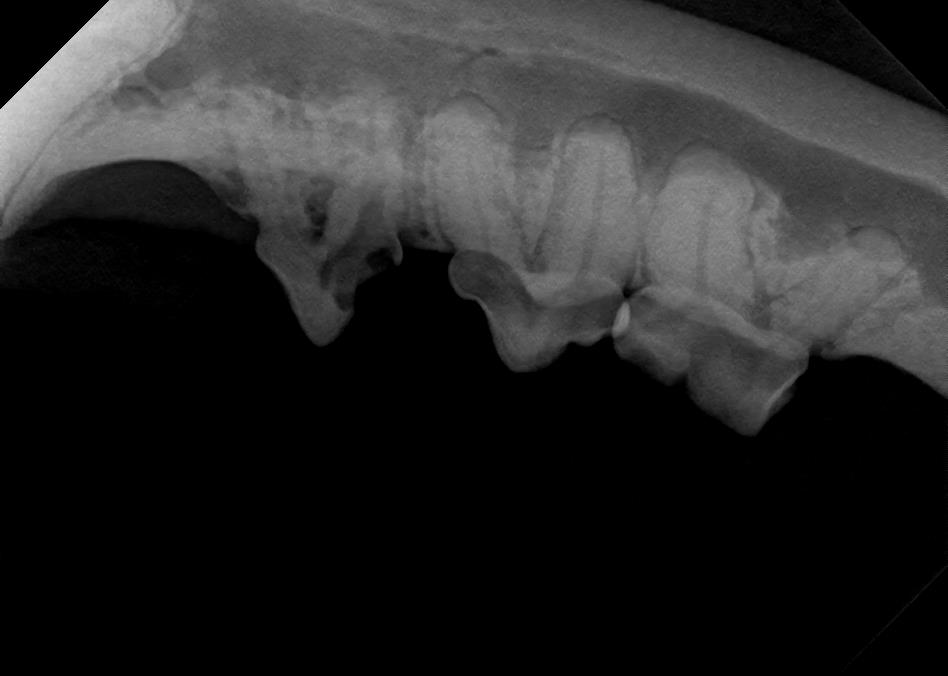

Examples of dental problems:

At A Couple of Vets, our animal hospital staff is well-versed in the latest dental cleaning techniques to remove plaque and tarter from the teeth’s surface as well as from below the gum line. We perform dental x-rays at every cleaning to ensure that the teeth are completely healthy. They may look good on the surface, but many problems occur below the gum line and are only visible with x-rays.